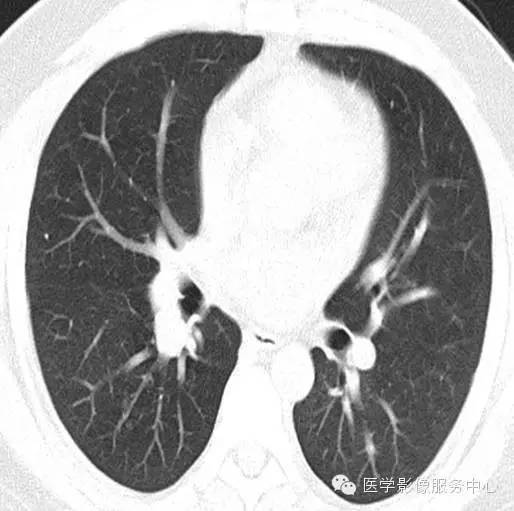

男, 26岁,因“咯血二十余日”入院 。患者一年余前无明显诱因下咯血,鲜红色,自诉无其他不适,至当地医院治疗后缓解,二十余日前无明显诱因下咯血,鲜红色,自诉无伴随症状。

2012年12月3号

影像分析:右侧肺门处见小团块状密度增高影,密度尚均匀,边缘毛糙,增强扫描病灶不均匀强化。

病理:肺神经内分泌瘤